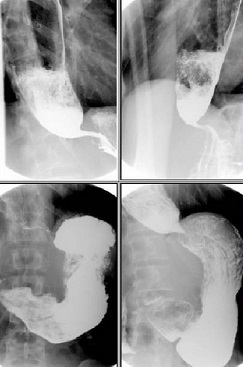

(钡餐检查)

可见狭窄上方食管明显扩张,积气积液,食物残渣

过去曾经做过这种食管的扩张手术,当时管了一段时间后又复发了,又过来复查。做钡餐发现贲门失弛缓症术后的表现,贲门还是有点紧,咽不下去。钡餐可以看到他食管扩张的非常明显,贲门细的和线一样了。患者咽不下去食物存在食管里他就扩张了,然后我们给他做了一个介入下的球囊扩张。通过把一个球囊放在贲门这个地方,然后往里充气,充气以后球囊慢慢的扩张,把患者这个狭窄给撑开了,狭窄就解除了,病就解决了,治疗非常简单。